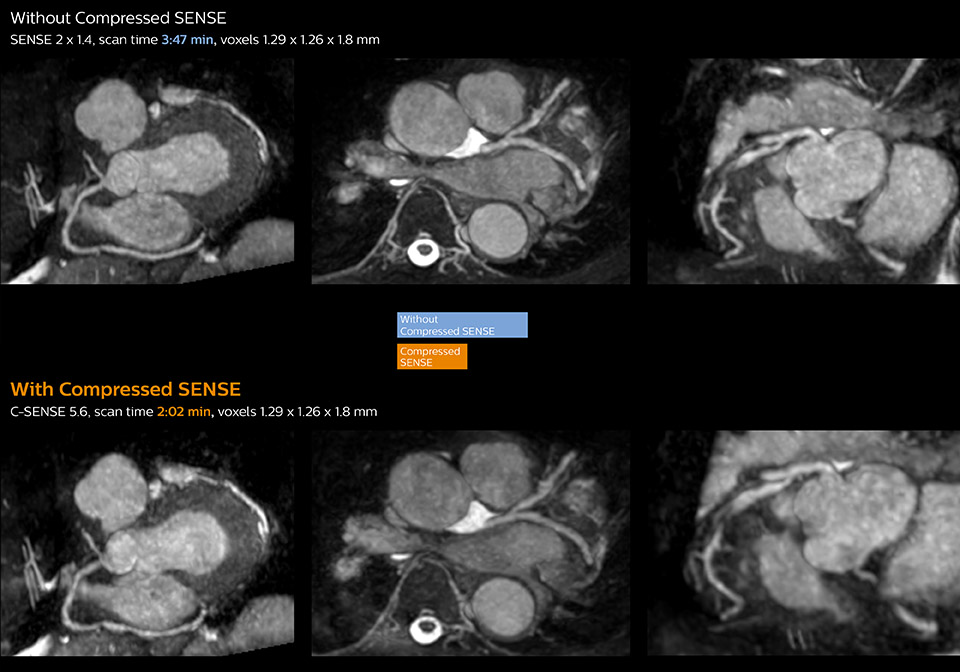

These images with and without Compressed SENSE were acquired on Ingenia 1.5T.

“Typically, in scans with high contrast, such as 2D balanced TFE cine, a quite high C-SENSE factor may be used. When we tried a higher C-SENSE factor, we saw still no significant influence on cardiac ejection fraction, but 2D image quality started to decline. For coronary imaging, we use a C-SENSE factor of 3 in 3D balanced TFE, or even up to 4 when contrast is high.”